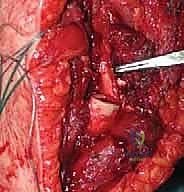

"Now, let's turn our attention posteriorly and laterally. We need to identify the quadrangular space. Carefully dissect between the teres minor superiorly and teres major inferiorly, and the long head of the triceps medially. Here, you will find the axillary nerve and the posterior humeral circumflex vessels. These are paramount for deltoid function. Meticulously dissect them free from any surrounding tissue or tumor involvement, tracing them distally towards the deltoid. Use fine instruments and gentle technique. Once identified, carefully loop them with vessel loops for easy identification and protection."

"Next, we must protect the radial nerve. This nerve courses around the posterior aspect of the humerus in the spiral groove, distal to the deltoid insertion. As we manipulate the humerus, especially as we prepare for our bone cut, this nerve is highly vulnerable. We'll place Chandler retractors around the posterior aspect of the humerus, ensuring they are protecting the radial nerve from any direct injury or excessive tension during retraction."

Figure 1: The radial nerve identified adjacent to the resected bone, highlighting the importance of its preservation.